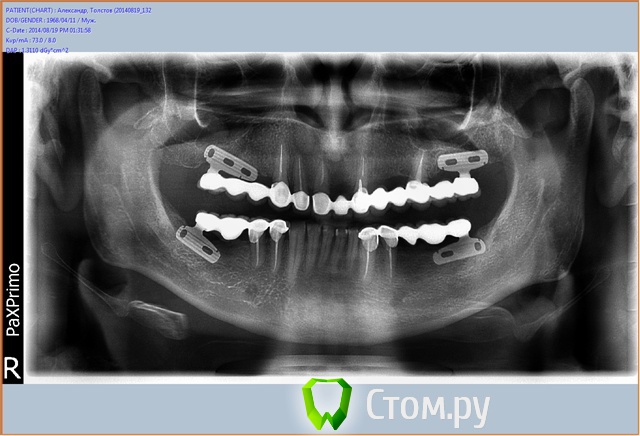

SergeiVar Опубликовано 3 сентября, 2014 Поделиться Опубликовано 3 сентября, 2014 вот тоже пример. левый верх стабилен, подвижности нет, но проблема есть. Ссылка на комментарий